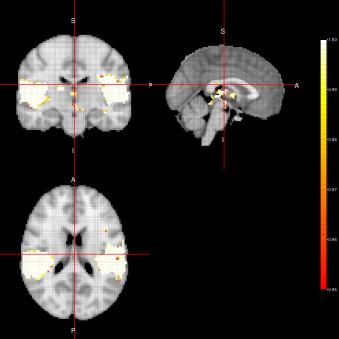

Figure 4: Activation Maps obtained for the ”voice localizer” example when using the FSTS algorithm under three different distributions (Marginal, Joint and LTT) related to the state parameter.

From figures 2, 3 and 4, we can see the activation maps obtained for the ”voice localizer” experiment using the method proposed in this work. From those images, we can say that the three algorithms (FEST, FFBS and FSTS) under the three different distributions (Marginal, joint and LTT or average distribution) successfully identify the temporal activation due to voice and non-voice sounds stimulation, nevertheless there are some slight differences among those maps worth mentioning. For instance, the maps obtained when using the FFBS algortihm allows for the identification of a broader activated region from the temporal cortex, however, on the other hand, it allows activations to appear (false-positive activations) on brain regions that should not be involved with this ”voice localizer” experiment. On the other hand, more conservative results seem to be obtained when using FEST and FSTS algorithms, but with less false activations.